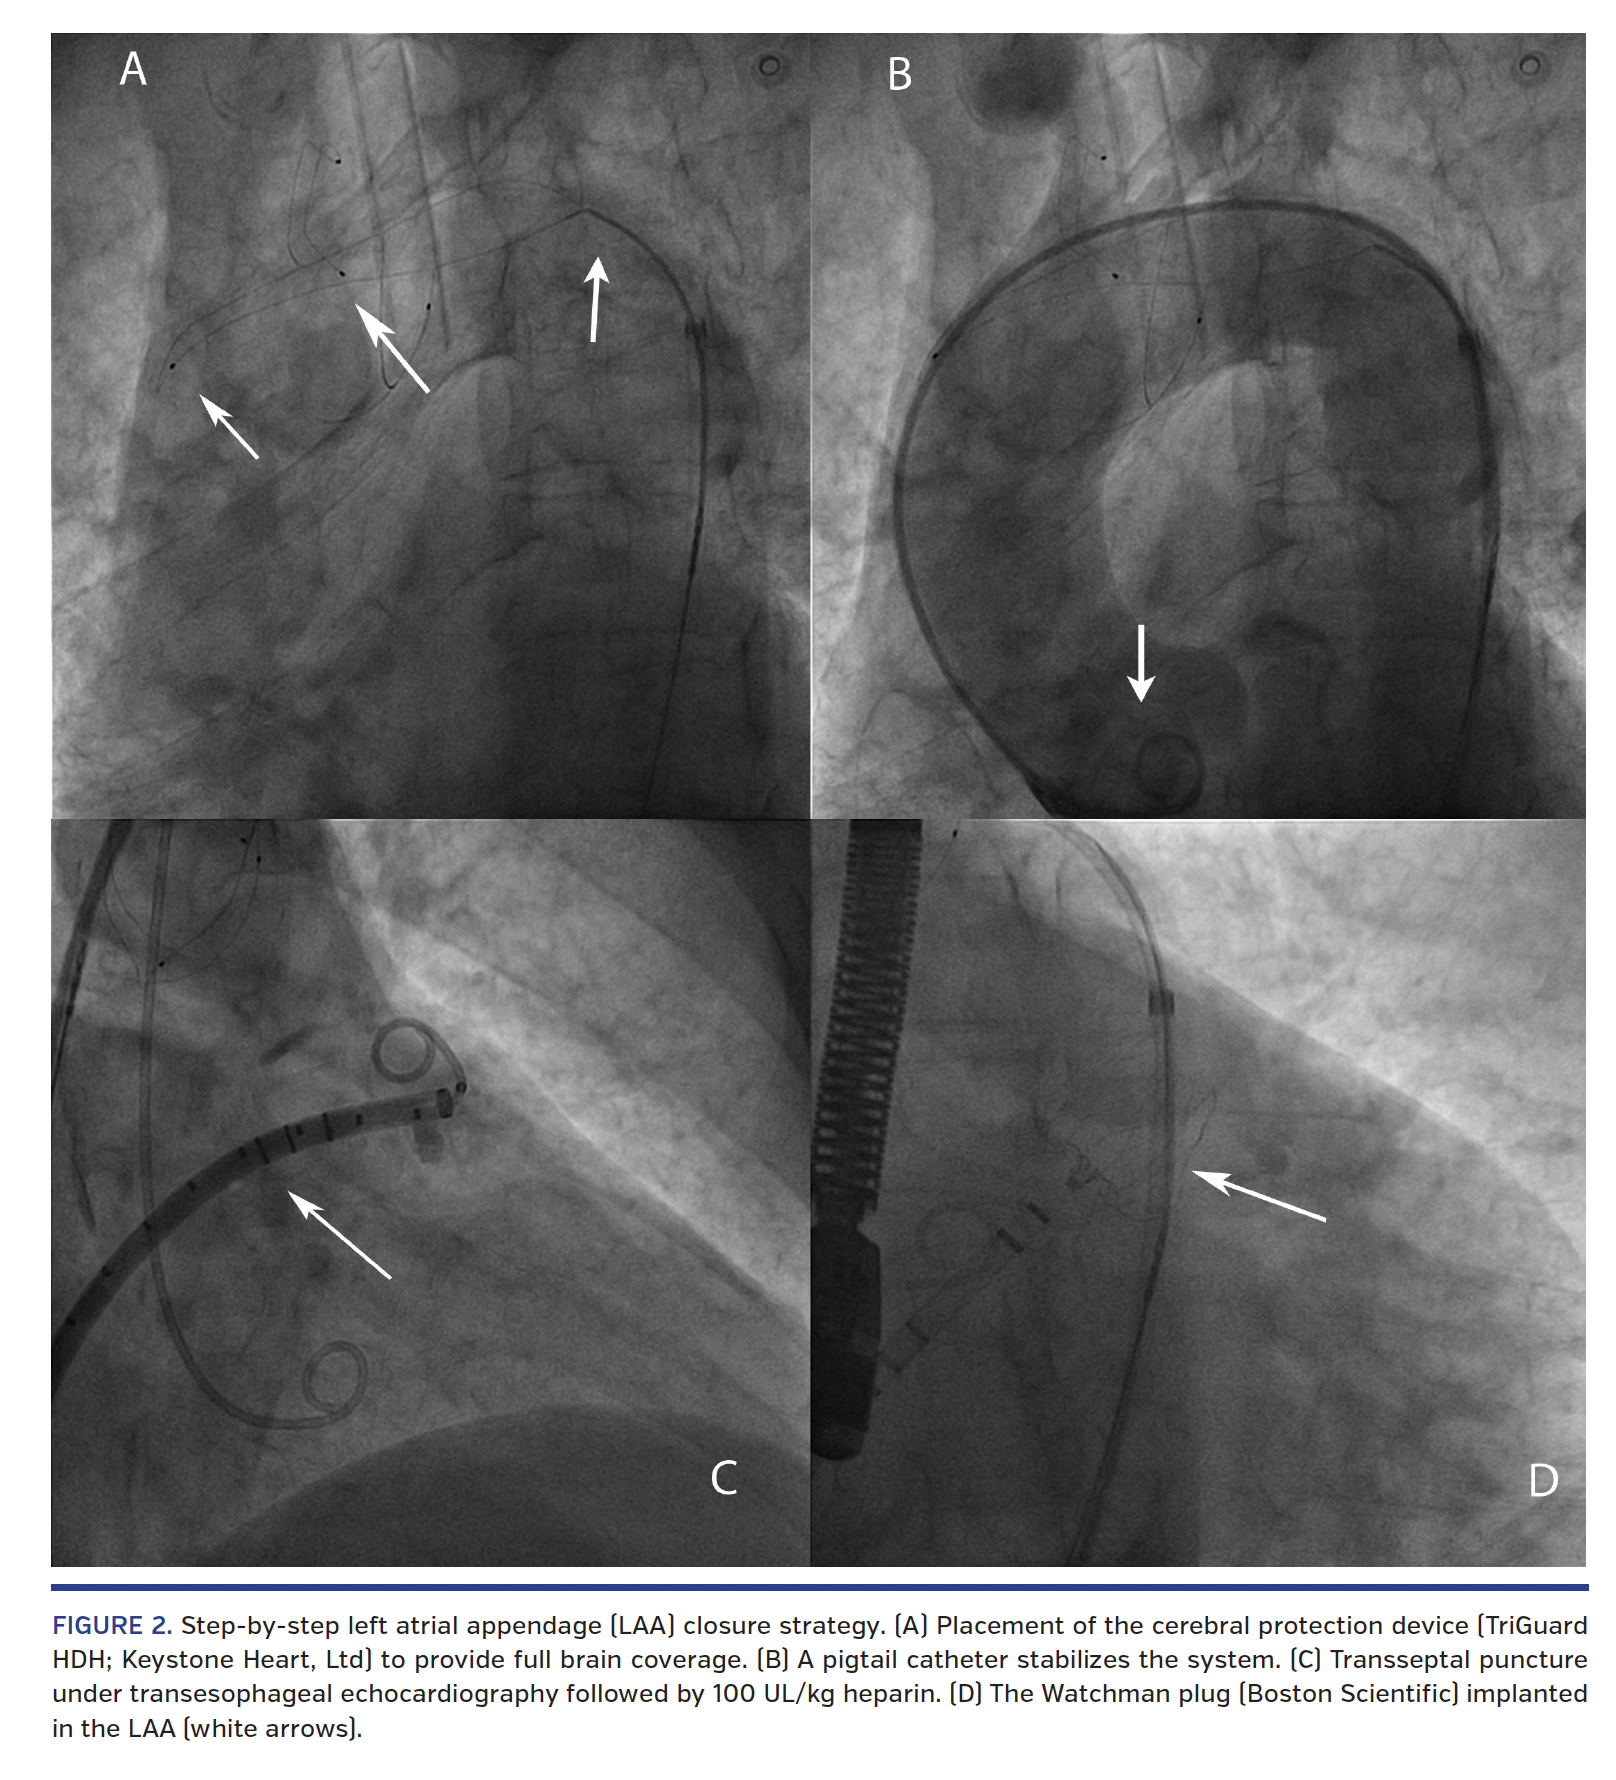

A 78-year-old male who was on warfarin presented with history of arterial hypertension, diabetes mellitus, remote spontaneous hemorrhagic pericardial effusion, permanent AF, and a previous hemorrhagic gastritis. He was transferred after a recent subdural hematoma under dabigatran to perform transesophageal echocardiography for the purpose of evaluating the feasibility of transcatheter LAA closure. Unfortunately, echocardiogram showed the presence of thrombus formation in the LAA. Anticoagulation with low-molecular-weight heparin and aspirin was resumed, but thrombus persisted in LAA at 1 month with ultrasound follow-up (Figure 1). After multidisciplinary discussion with a cardiac surgeon, neurologist, and interventionalist, we performed transcatheter LAA closure with TriGuard HDH embolic cerebral protection device (Keystone Heart, Ltd) (Figure 2). Then, the cerebral protection system was removed and angiographic control of the renal and mesenteric arteries was performed to exclude distal embolization. We didn’t perform angiography of the supraaortic trunks because of the lack of any neurological dysfunction. LAA closure is a valuable alternative in patients with absolute contraindication to long-term anticoagulation due to high bleeding risk. Although the presence of thrombus in the LAA is a prohibitive condition to the invasive procedure, the cerebral distal protection device allowed to safely conduct transcatheter LAA closure, reducing the risk of cerebral embolization linked to periprocedural thrombus mobilization or manipulation. The patient was discharged with dual-antiplatelet therapy (aspirin 100 mg and clopidogrel 75 mg daily) for 1 month.